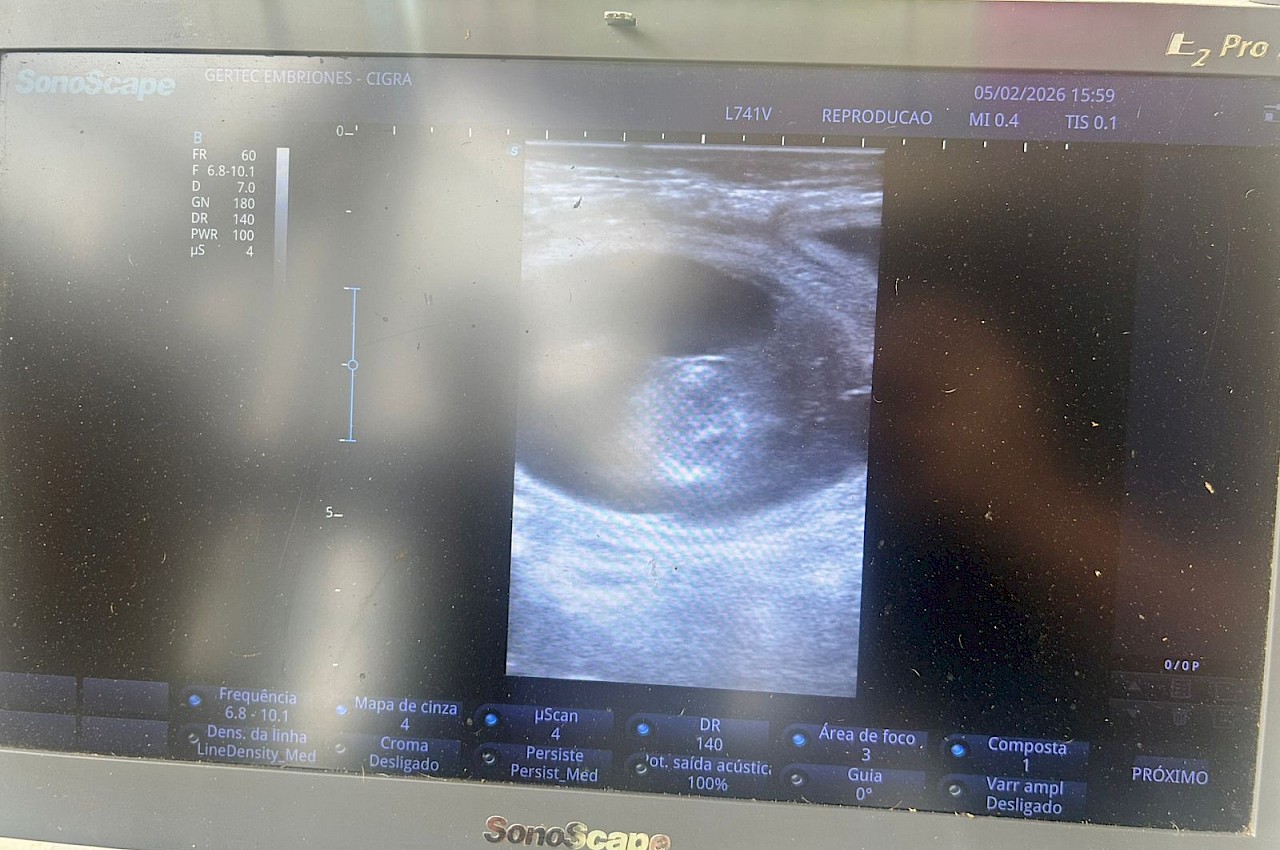

Como parte del proceso, una vez realizada la transferencia, el ISA interviene a los 60 días, momento en el cual el especialista de la empresa efectúa una palpación con ultrasonografía para confirmar la preñez. Tras la verificación, se emite el certificado correspondiente, documento indispensable para formalizar el aseguramiento de los vientres.